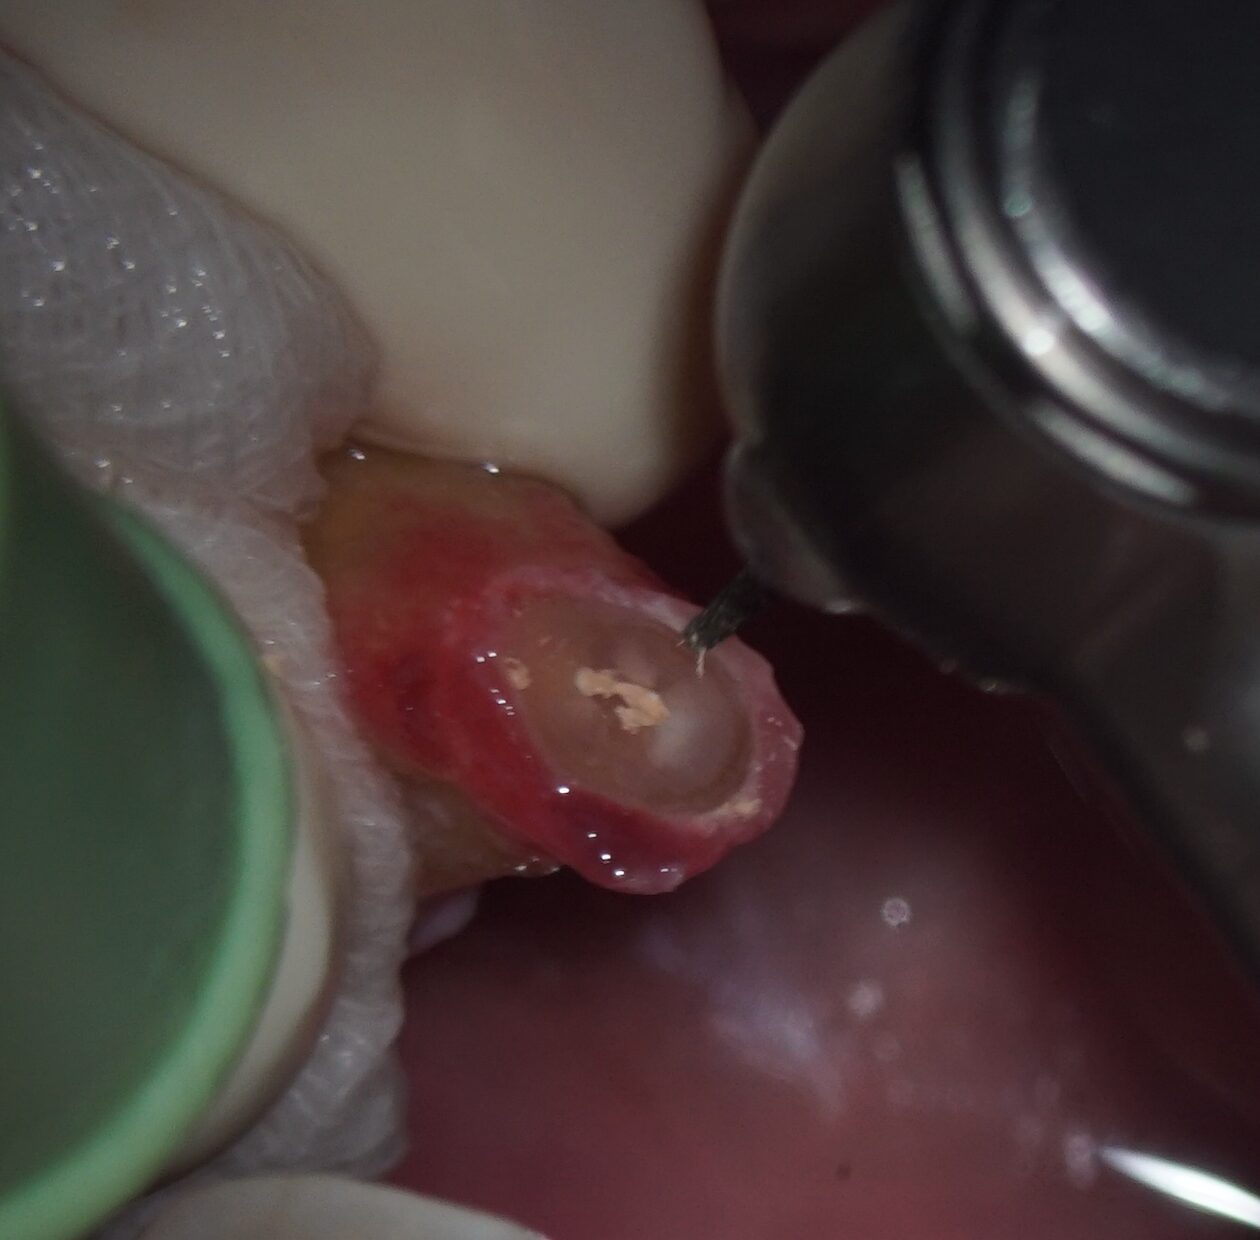

• 歯根端切除術で摘出した歯根と肉芽組織、黄色い色をした菌塊(細菌のコロニー)が多数見られました(黄色丸内のつぶつぶ)。これが非治癒の原因、根尖孔外に飛び出した感染源です。